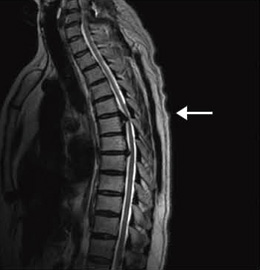

症例4:胸椎後縦靭帯骨化症

55歳,男性。数年前から下肢のしびれ感と脱力が進行した。第5,6胸椎レベルで後縦靭帯の骨化が認められ,胸髄が強く圧迫されていた。

T2WI,FSE,TR/TE:3500/117,FOV:350mm,スライス厚:4.0mm